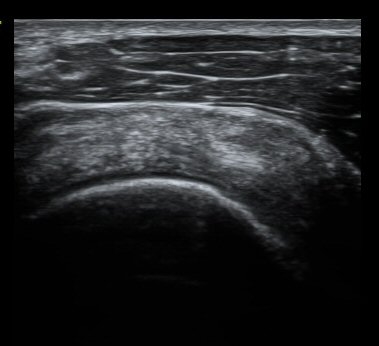

ÃÊÀ½ÆÄ °Ë»ç

ȸÀü±Ù°³°£°Ý Ⱦ´ã³à°Ë»ç¿¡¼­ ƯÀÌ ¼Ò°ßÀ» º¸ÀÌÁö ¾ÊÀ½(±×¸² 1).

À̵ιڱٰí¶û¿¡¼­ À̵ιڱÙÀÌ Á¤»óÀûÀ¸·Î °üÂûµÇ°í ƯÀÌ ¼Ò°ßÀ» º¸ÀÌÁö ¾ÊÀ½(±×¸² 2).

ȸÀü±Ù°³°£°Ý ³»Ãø Ⱦ´Ü¸é°Ë»ç¿¡¼­ °üÂûÇÑ °ß°©ÇÏ±Ù°Ç »óºÎ Á¾´Ü¸é°Ë»ç¿¡¼­ ¹Ì¼¼ÇÑ °£±ØÀÌ

°üÂûµÊ(±×¸² 3, 4). °ß°©ÇÏ±Ù°Ç È¾´Ü¸é°Ë»ç¿¡¼­µµ °ß°©Çϱٰdz» °£±ØÀÌ °üÂûµÊ(±×¸² 5).

±Ø»ó°Ç Á¾´Ü¸é°Ë»ç¿Í Ⱦ´Ü¸é°Ë»ç¿¡¼­ ±Ø»ó°Ç³» ¹Ì¼¼ÇÑ °£±ØÀÌ °üÂûµÊ(±×¸² 6, 7, 8).

°ßºÀ ¿ÜÃø¿¡ ŽÃËÀÚ¸¦ ´ë°í ½ÃÇàÇÑ Ãæµ¹°Ë»ç¿¡¼­ °ßºÀ ¿ÜÃø¿¡ ¼ö¾×Àú·ù°¡ °üÂûµÇ¾ú´Ù.(±×¸² 9).